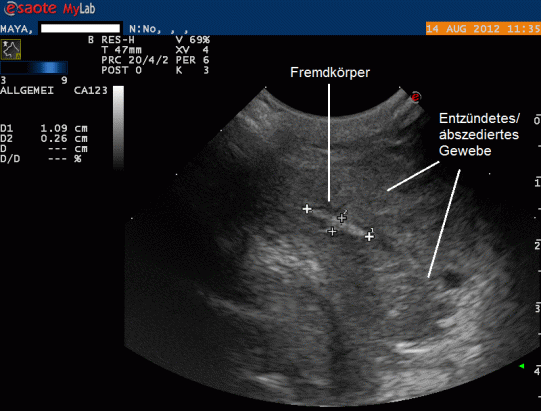

Der Umstand, dass die Schwellung rezidivierte, macht uns misstrauisch und bewirkt, dass der Knoten mittels Ultraschall genauer untersucht wird. Inmitten eines Gewebes, welches kleine flüssigkeitsgefüllte Hohlräume (wahrscheinlich Abszesse) enthält, findet sich eine stark echogene (d.h. "weisse") längliche Struktur von etwa 11 mm Länge und knapp 3 mm Durchmesser - offensichtlich handelt es sich hier um einen Fremdkörper!